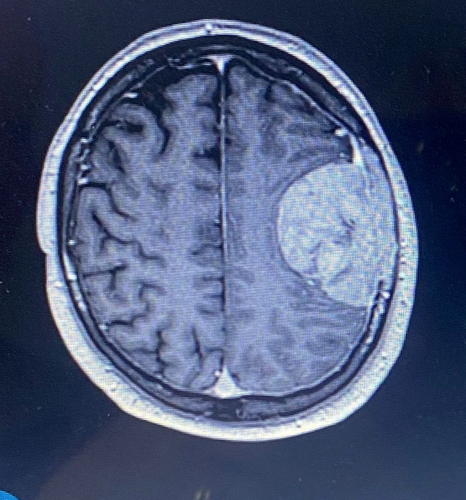

He was blue-lighted to Southmead Hospital, Bristol, where a CT scan revealed a mass on the brain.

Stuart's speech fluctuated, and he was diagnosed with a meningioma - a slow-growing tumor.

After being blue-lighted to Southmead Hospital, a CT scan revealed that Stuart had a mass on the brain.

Stuart’s speech fluctuated, and he was prescribed steroids. Surgeons advised that, because there was no evidence of cancer elsewhere, it was likely to be a slow-growing tumor that Stuart could have had for years.